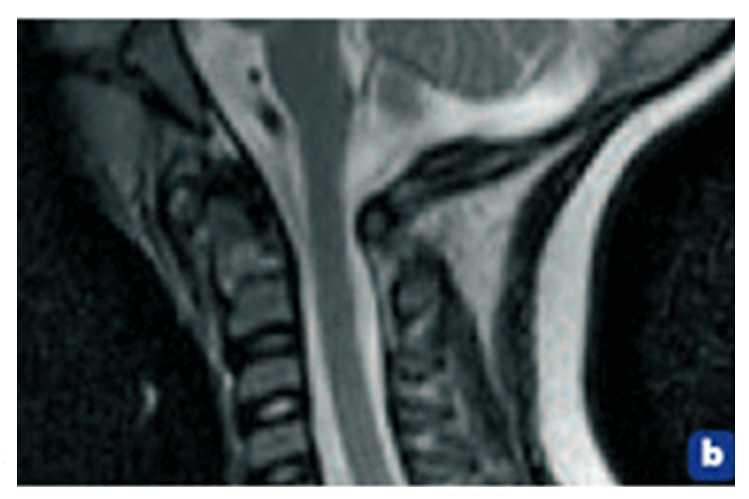

L’article relate la recherche diagnostique qui se conclue sur une spondylodiscite cervicale atlo-axoïdienne, sans avoir retrouvé le moindre germe, et avec l’appui d’un cliché de son IRM cervicale que l’on peut visualiser ci-dessous, puis agrandie.

Si l’on reprend les lignes géométriques identifiables sur cette IRM, il apparait que :

Lignes par calque de l’IRM de la fillette de trois ans.

On peut déjà en conclure que ce cliché d’IRM comporte quelques anomalies non négligeables de géométrie méritant une analyse plus poussée.

En premier l’angle entre l’odontoïde et l’ensemble de la deuxième cervicale est particulièrement inquiétant et attire tout de suite l’œil. Ci-dessus il est mesurable à 109°, alors que d’après Kahle, H Leonhardt et W Platzer, Anatomie Tome 1 édition Flammarion Médecine-sciences 2° édition, 9° tirage 1991, page 38, l’odontoïde est verticale avec l’ensemble pédicules-lames-épineuse de l’axis horizontal, soit un angle de 90°.

Cette première anomalie de l’IRM ne peut signifier qu’une fracture de la base de l’odontoïde.

– Si l’on se réfère au tracé des repères osseux du canal rachidien, on a la surprise de constater que chez la fillette, le canal rachidien est soumis à un effet de coupe-cigare en regard de l’atlas :

On peut constater que le positionnement antéro-postérieur de l’atlas, s’il est satisfaisant par rapport à l’occiput et au sphénoïde, il est anormalement antérieur par rapport à l’axis mais surtout par rapport à la troisième cervicale, chez la fillette. Ceci signifie une luxation antérieure de l’atlas sur l’axis, ce qui est fréquent en association avec les fractures déplacées de l’odontoïde. Il faut pour cela une rupture des ligaments atlo-axoïdiens postérieurs.

Enfin, si l’on prend le temps de mesurer les diamètres antéro-postérieurs de ce canal rachidien :

Il est clair que la luxation de l’atlas sur l’axis réduit le canal rachidien en regard de l’atlas.